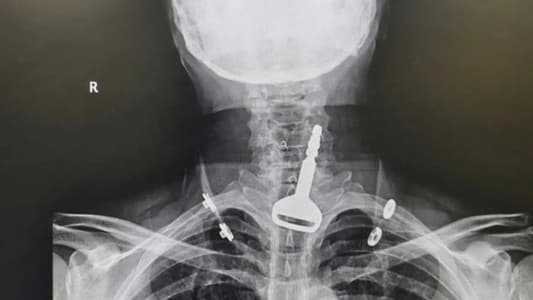

وأوضحت صحة مدينة القنفذة أن المريض البالغ من العمر 49 عاماً، وصل لقسم الطوارئ وهو يعاني من انسداد بمجرى التنفس ليتضح بعد الفحص السريري والأشعة وجود مفتاح سيارة عالق في القصبة الهوائية.

وتقرر فورا إدخال المريض قسم العمليات وتكثيف العناية الصحية له لكونه مريض قلب، وتم إجراء التدخل الجراحي عن طريق المنظار واستخراج المفتاح، ومن ثم متابعة الحالة عن طريق قسم التنويم لحين استقرار حالته الصحية وخروجه بالسلامة.

واعترف الأربعيني للأطباء المعالجين بأنه ابتلع المفتاح أثناء لهوه به ما تسبب له في حالة اختناق جزئي تطلب التدخل الجراحي لاستخراج الجسم المعدني العالق